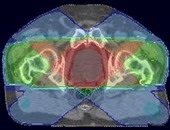

Diagrama care arată îndepărtarea unei părți din stomac în etapa Billroth I

Diagrama arată anatomia stomacului dupa operatie Billroth I

Diagrama arată anatomia stomacului înainte de operația de suprapunere în formă de Y anastomoza Roux

Diagrama arată conexiunea esofagului, duoden 12 a intestinului subțire și după operația suprapuse anastomoză în formă de Y Roux

Diagrama arată conexiunea esofagului, duoden 12 a intestinului subțire și după operația suprapuse anastomoză în formă de Y Roux

Diagrama care arată îndepărtarea unei părți a esofagului și a stomacului atunci când ezofagogastrektomii

Diagrama arată anatomia stomacului după ezogogastrektomii